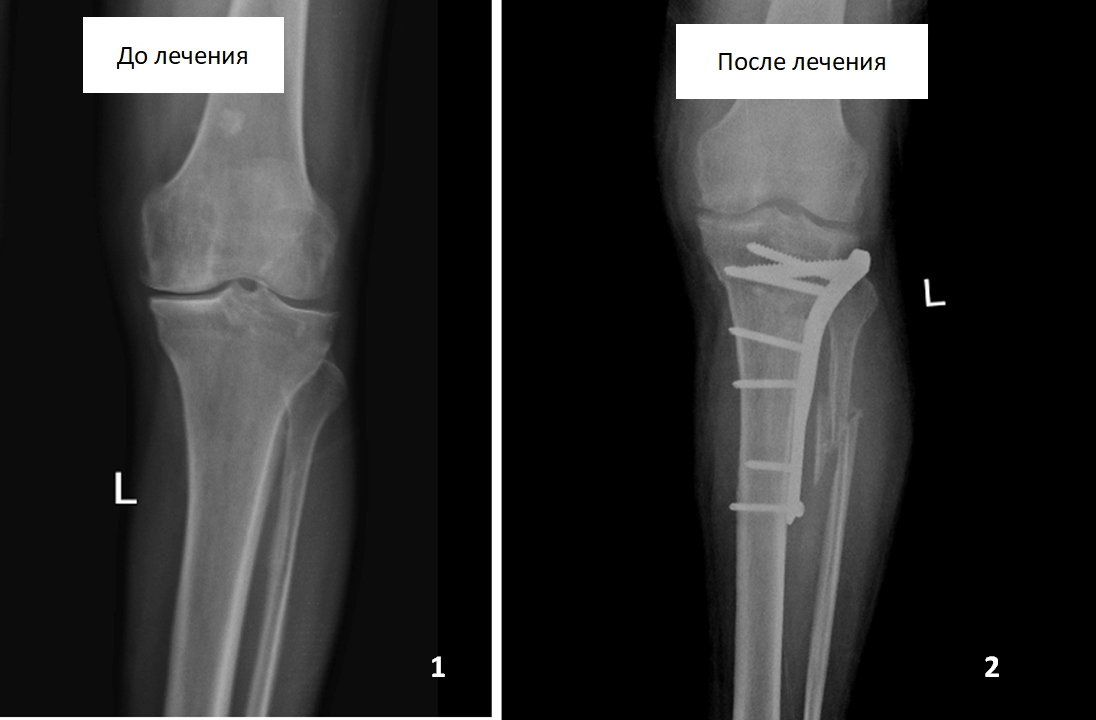

У жінки на тлі дисплазії кульшового суглоба розвинулася виражена установча вальгусна деформація лівої гомілки, яка супроводжувалася значними болями в області колінного і кульшового суглобів, які виникали відразу ж при початку ходьби. У спеціалізованому медзакладі пацієнтці було запропоновано виконати протезування кульшового і колінного суглобів, від яких вона відмовилася.

Ми одномоментно виконали відновлювальні оперативні втручання в області гомілки і кульшового суглоба. Після реабілітаційного лікування пацієнтка повноцінно користується лівою ногою і може тривалий час ходити пішки без будь-яких болів в суглобах.